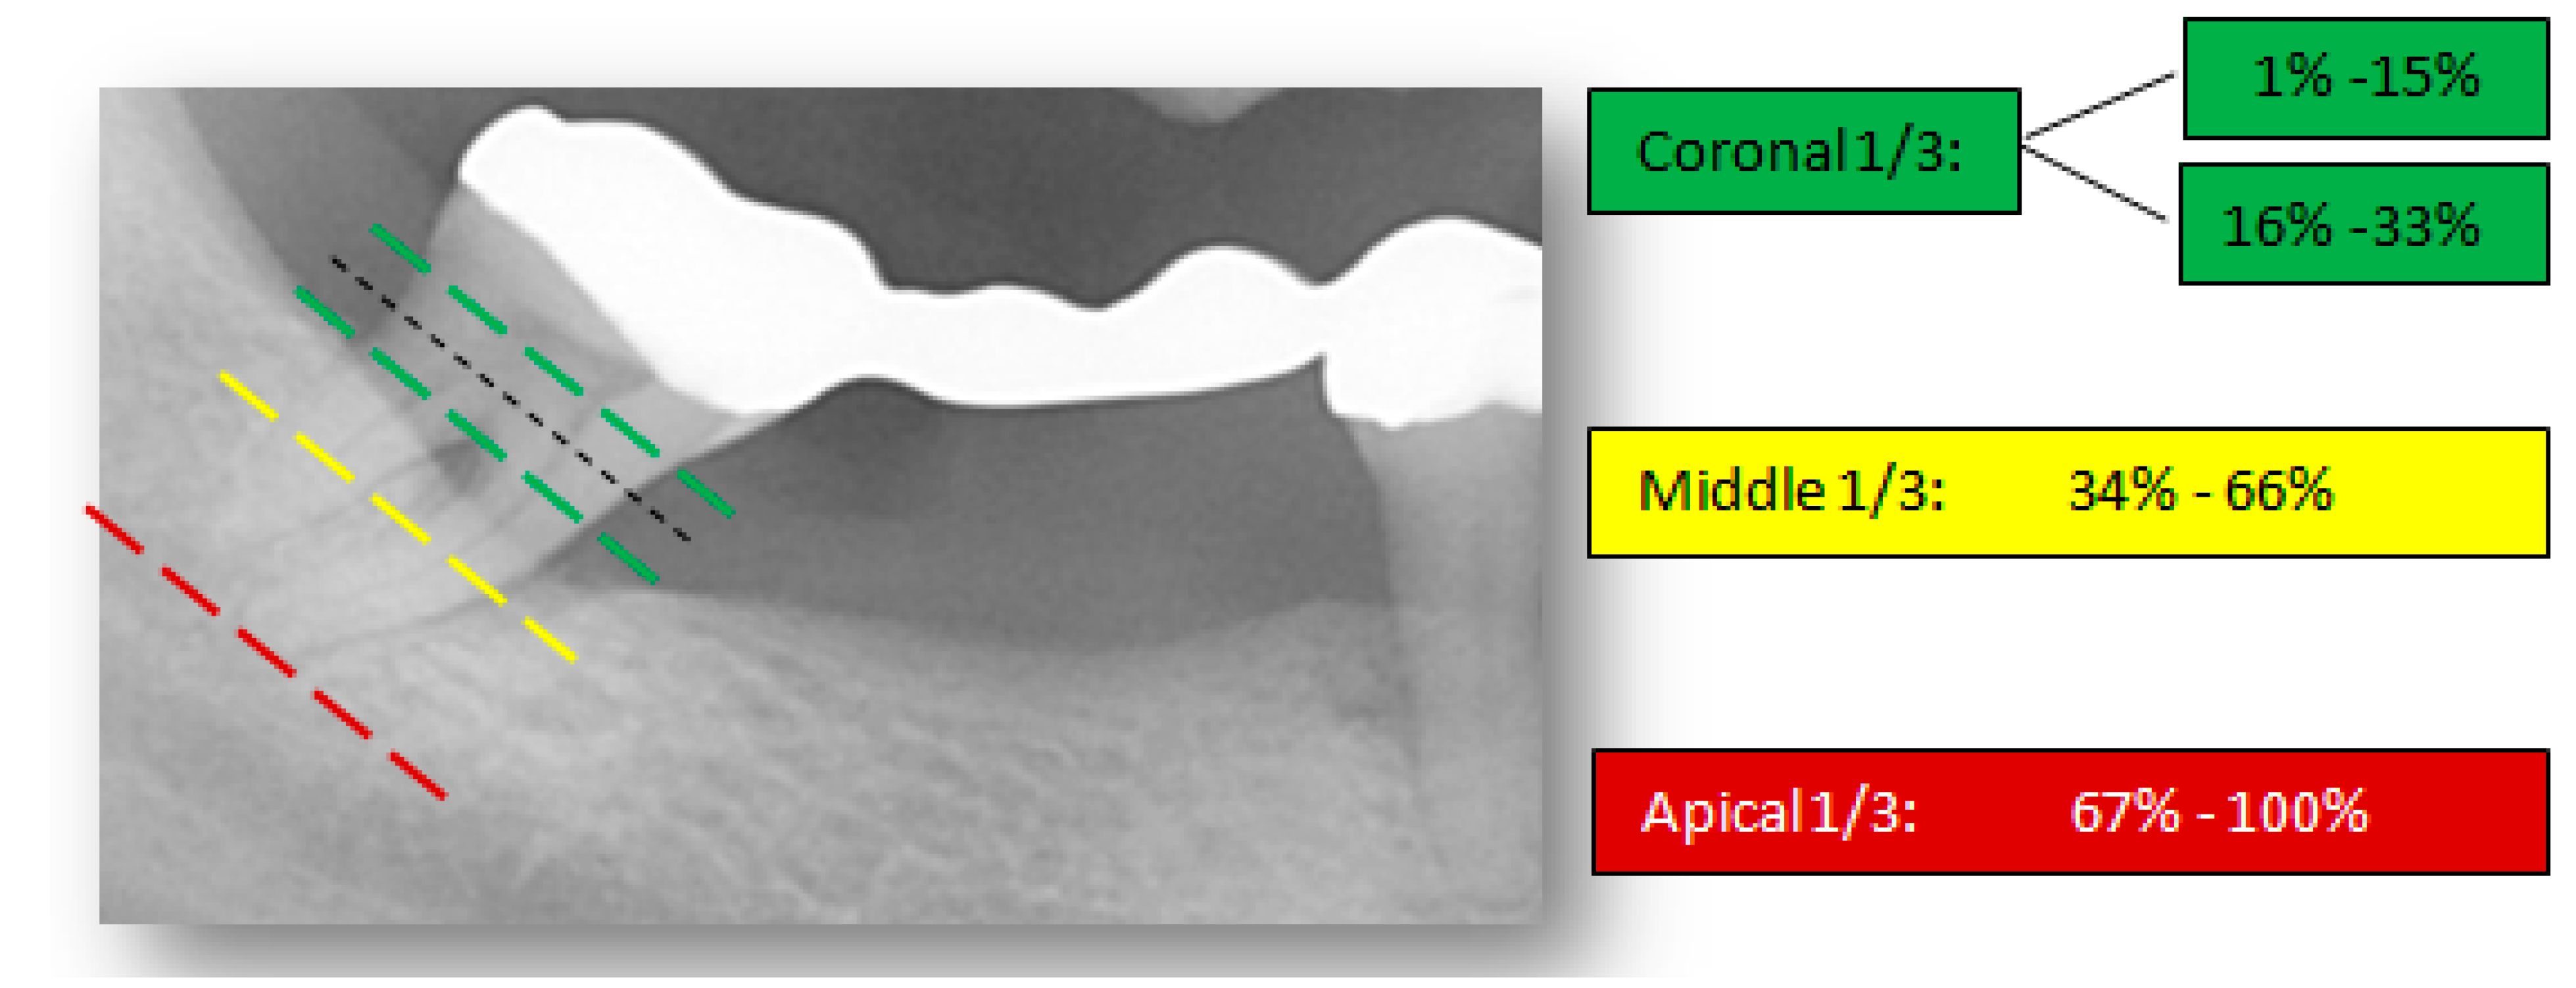

The proposed visual and radiographic interpretation techniques to determine the severity and pattern of iABL are illustrated in Figure 2 and Figure 3.

Figure 2.

Visual interpretation of bone loss severity. The ‘worst’ tooth in each quintet is visually divided into coronal, middle, and apical thirds and the percentage of alveolar bone loss is measured accordingly.

The percentages of iABL were purposefully selected in agreement with the severity assessment via staging in the new periodontal classification system [25]. The proposed scoring codes thus correspond to the coronal, middle, and apical thirds of a root.